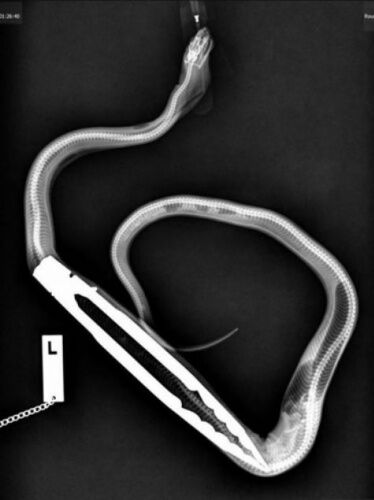

Bu ilginç hayvanları görenler hayret etti